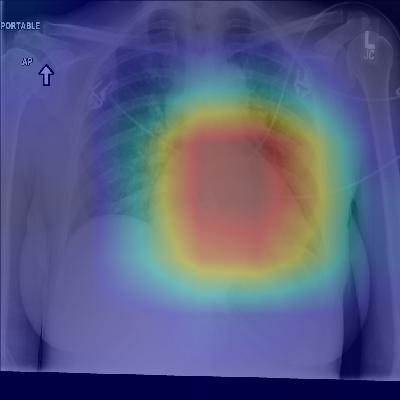

(f) Patient with congestive heart failure and cardiomegaly (enlarged heart). The model correctly identifies the enlarged cardiac silhouette.

Figure 2: CheXNet localizes pathologies it identifies using Class Activation Maps, which highlight the areas of the X-ray that are most important for making a particular pathology classification. The captions for each image are provided by one of the practicing radiologists.

Figure 2 shows several examples of CAMs on the pneumonia detection task as well as the 14-class pathology classification task.